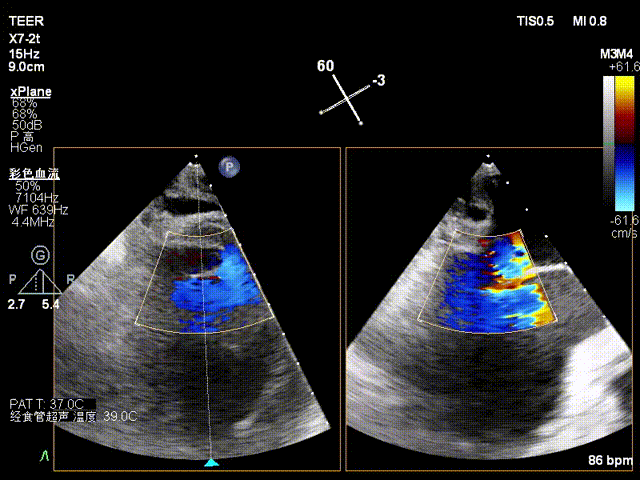

X-plane2区彩色

X-plane 2区彩色

经食道超声检查提示:二尖瓣瓣叶增厚冗长2区后瓣脱垂呈连枷样改变,考虑Barlow’s综合征。评估解剖结构:前叶长度:3.3cm,后叶长度:2.8cm,脱垂宽度:26mm,脱垂高度:19mm,瓣口面积:7.5cm²。